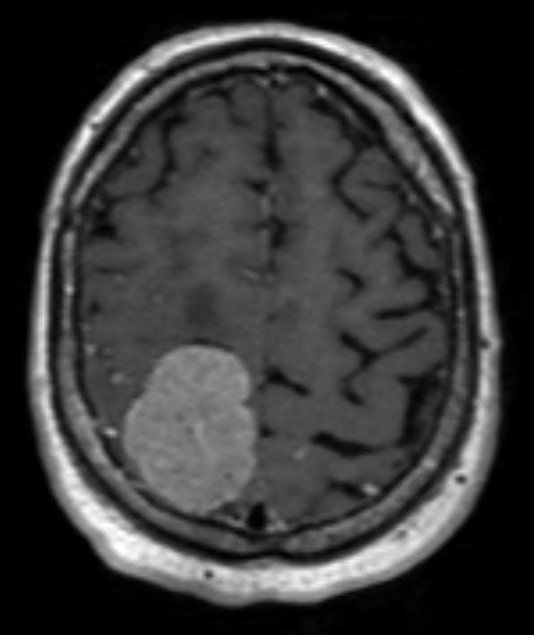

При МРТ-обследовании было выявлено крупное, около 5 см, внемозговое новообразование в лобной и теменной областях. Оно и являлось причиной приступов и слабости в руке и ноге. На момент поступления в стационар пациент не мог вставать и обслуживать себя.